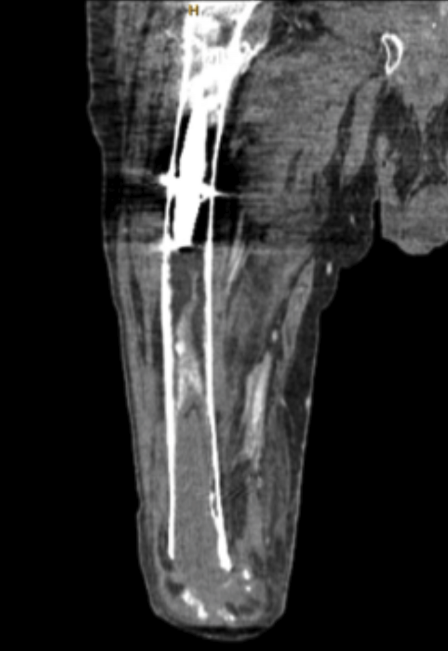

The patient underwent free gracilis muscle flap intramedullary canal dead space obliteration and stump coverage (Figure 1). The intramedullary canal had been thoroughly reamed in prior debridement and antibiotic bead placements. The ipsilateral gracilis muscle was small and atrophic from distal disinsertion at initial amputation. Thus, as the contralateral gracilis approximated the femoral defect, making it a suitable option for dead-space obliteration, it was harvested as a free muscle-only flap in the usual fashion. A cuff of the deep femoral artery and vein was taken to manage the size mismatch between the stump of the femoral artery and the donor vessel; this facilitated a functional end-to-end anastomosis. The deep femoral artery was not reconstructed following harvest and the donor was closed primarily over a drain. To preserve blood supply to the distal stump, an end-to-end patch hand-sewn anastomosis with stump superficial femoral artery and vein was performed. Two 3.5-mm drill holes were made by orthopedics in the proximolateral femur, and a prolene suture anchor was passed down the canal anterograde with a pediatric feeding tube. The suture and muscle flap lengths were noted prior to inserting the free gracilis in the medullary canal in order to approximate complete obliteration of femoral dead space. The suture was secured to the tendinous portion of the distal gracilis; the flap was then pulled retrograde into the femoral canal with minimal resistance and secured to the drill holes proximally without excessive tension (Figure 1). The ease of passage into the canal along with the avoidance of excess tension suggested minimal risk of flap vascular compromise from compression. The gracilis flap covered the distal aspect of the transfemoral amputation and obliterated the dead-space within the intramedullary canal (Figure 2). A wound vac was applied, as primary closure was not possible due to tissue edema. Anticipating future prosthesis at the stump and atrophy of the gracilis, this stump was allowed to close with continued vac therapy rather than skin grafting.

The patient completed an additional course of long-term antibiotic therapy with cefepime. Six months after the procedure, the patient’s stump was fully healed with no symptoms of osteomyelitis. The donor site healed fully without complication. The patient was subsequently fitted for a prosthesis and resumed ambulation after a short course of rehabilitation. CT at this time demonstrated continued presence of the gracilis within the femoral canal and no evidence of osteomyelitis (Figure 2). One year postoperatively, the patient remains ambulatory without recurrence of osteomyelitis.